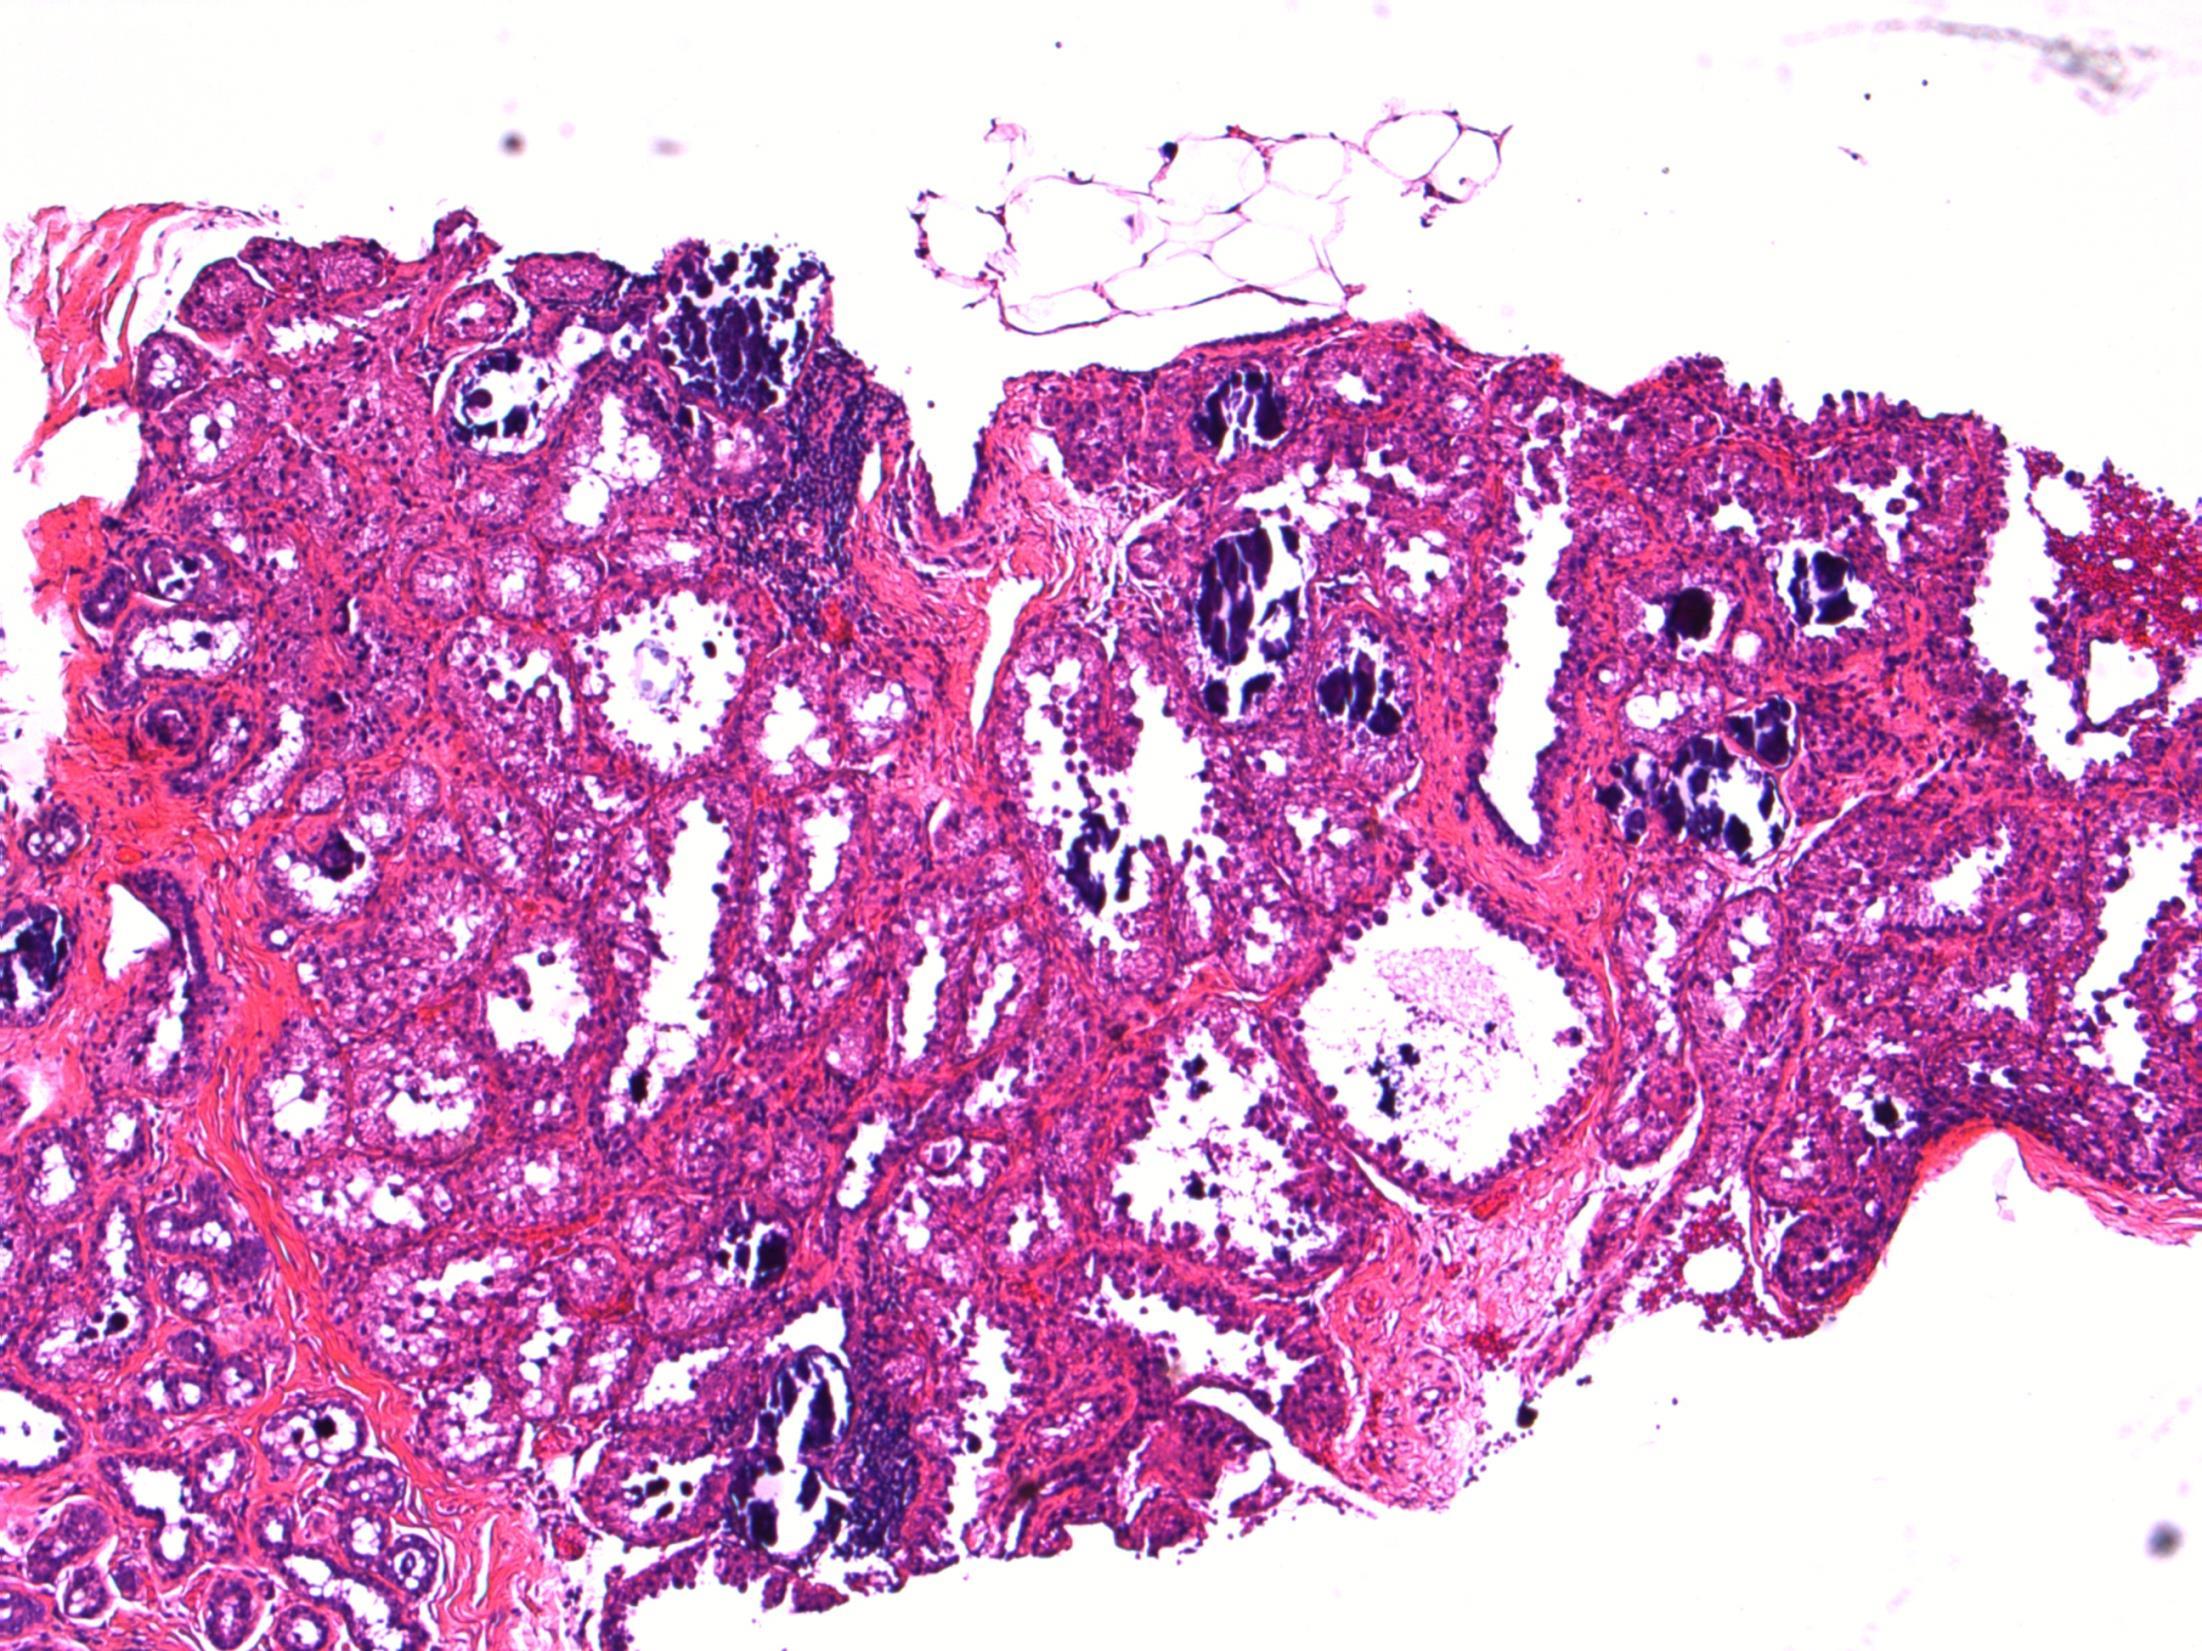

50F, Breast screening shows a 4mm area of microcalcification in lower outer right breast. Stereotactic core biopsy taken

• Breast cores – Focal lactational change with microcalcifications (B2)

Case 4

Focal lactational change

Description: Dilated acini with secretions, vacuolated cytoplasm and hobnail appearance. Microcalcifications associated. No evidence of DCIS or invasive malignancy.

Diagnosis: Lactational change with microcalcifications (B2)

Plan: Correlate with radiology and clinical examination at the MDT Correlate with any cytology, if perormed.

Comments:

• Biopsied because of microcalcifications .

• Usually seen associated with pregnancy/breast-feeding, unlikley in this age as 50 years old.

• Can be seen in non-pregnant (even nulliparous) women – usually focal, no clinical significance, like in this case.

• Can have associated ADH/DCIS, not present in this case.

• No further treatment required.

3.5 Importance of radiological correlation at MDT 3.0 B coding, significance 2.5 Description with diagnosis / DD 2.0 Other benign diagnosis with no mention of lactational change 1.5 Atypical diagnosis 1.0 Malignant diagnosis Case

4